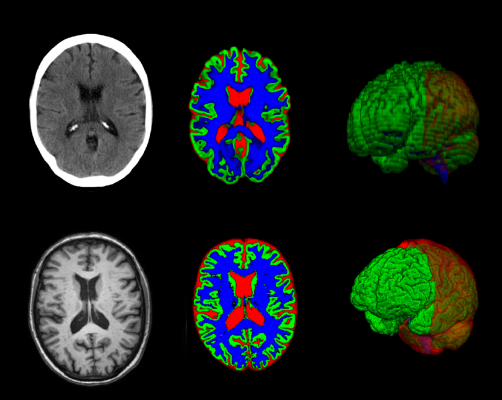

Examples of CT and MR scans of the same patient where the CT image was segmented into different tissue classes with the new software developed by the research group (top row) and the MR image with an existing software (bottom row).

October 20, 2023 — In certain cases, a new method can provide as much information from brain images taken with computed tomography (CT) as images captured with magnetic resonance imaging (MRI). The method, presented in a study from the University of Gothenburg, could enhance diagnostic support, particularly in primary care, for conditions such as dementia and other brain disorders.

The new software can provide diagnostic support for radiologists and other professionals who interpret CT images. It has been created using deep learning, a form of artificial intelligence (AI). The software has been trained to transfer interpretations from MRI images to CT images of the same brains.

“It is now possible to measure the size of different structures or regions of the brain in a similar way to advanced analysis of MRI images. The software makes it possible to segment the brain’s constituent parts in the image and to measure its volume, even though the image quality is not as high with CT.”